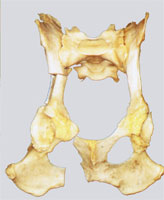

Nach der Osteotomie kann das Acetabulum mit den Segmenten des Os ilium und Os ischium um den vorbestimmten Winkel rotiert werden (Abb. 7 und 8).

DBO Rotation um 30°

Abbildung 7: Optimierte Überdachung nach Rotation um 30°

DBO am Knochenmodell

Abbildung 8: Ergebnis der Dreifachen Beckenosteotomie am Knochenmodell